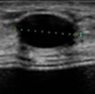

胸部自体脂肪移植前后 超声波

颜美整形医院为了确保术前状态及与术后无副作用,为患者提供术前术后超声波检查.